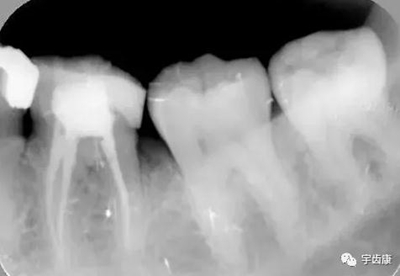

樁固位形(增加固位形和抗力形)

X線閱片知識